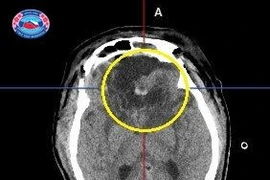

Kết hợp kỹ thuật định vị thần kinh và vi phẫu giúp lấy các khối u nằm sâu trong não mà không gây các tổn thương não lành xung quanh giúp nâng cao hiệu quả, chất lượng điều trị cho người bệnh.